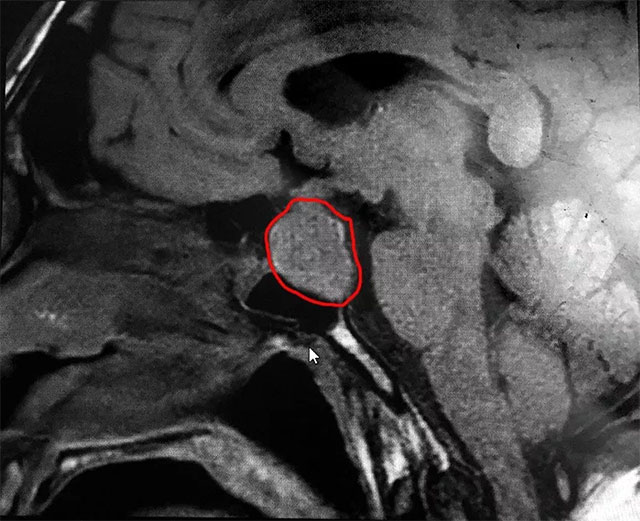

▲ 標(biāo)記處為患者腫瘤部位